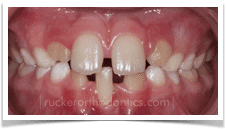

Crowding: This is one of the most common reasons for early orthodontic treatment. Simply put, adult sized teeth are trying to fit in child sized jaws. This mismatch creates an obvious dental situation in which arch development, or widening, through orthodontic treatment is required to create space for permanent tooth eruption. Early correction can also prevent more serious complications such as tooth impactions.